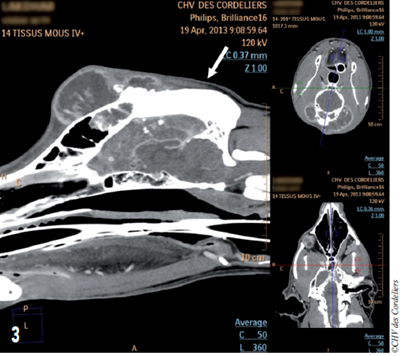

- Latéralement, la masse déborde de façon plus importante du côté gauche avec un envahissement du processus zygomatique de l’os frontal et s’étend 1 cm en arrière de l’œil (photo 3).

Photo 3 : Aspect tomodensitométrique de la masse en vue sagittale : la masse s’étend très caudalement (flèche).